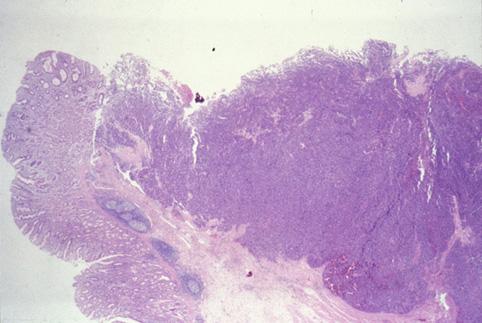

Cáncer Subcelular del Estómago (Endocrinoma) y que había metastatizado al Hígado

Tumor Epitelial Maligno/Otros

estómago(región)/cardias

Tipo 1(Tipo protuído)/

grado de penetración